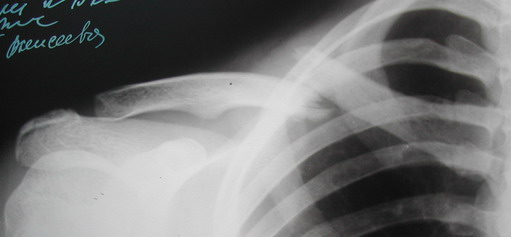

Во время стажировки в Австрии не мог не поинтересоавться, как австрийские хирурги лечат переломы ключицы. Оказалось, при переломах без смещения или с небольшим смещением накладывают восьмиобразную повязку, в остальных случаях выполняют остеосинтез пластинами.

После этого разговора стал интересоваться "качеством жизни" и, в частности, "качеством сна" у больных с переломами ключицы. Оказалось, что, действительно, спать в повязке нелегко, особенно в первые дни.